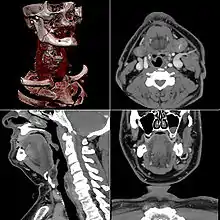

Neck

Contrast CT is generally the initial study of choice for neck masses in adults.[37] CT of the thyroid plays an important role in the evaluation of thyroid cancer.[38] CT scan often incidentally finds thyroid abnormalities, and so is often the preferred investigation modality for thyroid abnormalities.[38]

Presentation

- Average intensity projection

- Maximum intensity projection

- Thin slice (median plane)

- Volume rendering by high and low threshold for radiodensity

The result of a CT scan is a volume of voxels, which may be presented to a human observer by various methods, which broadly fit into the following categories:

- Slices (of varying thickness). Thin slice is generally regarded as planes representing a thickness of less than 3 mm.[90][91] Thick slice is generally regarded as planes representing a thickness between 3 mm and 5 mm.[91][92]

- Projection, including maximum intensity projection[93] and average intensity projection

- Volume rendering (VR)[93]